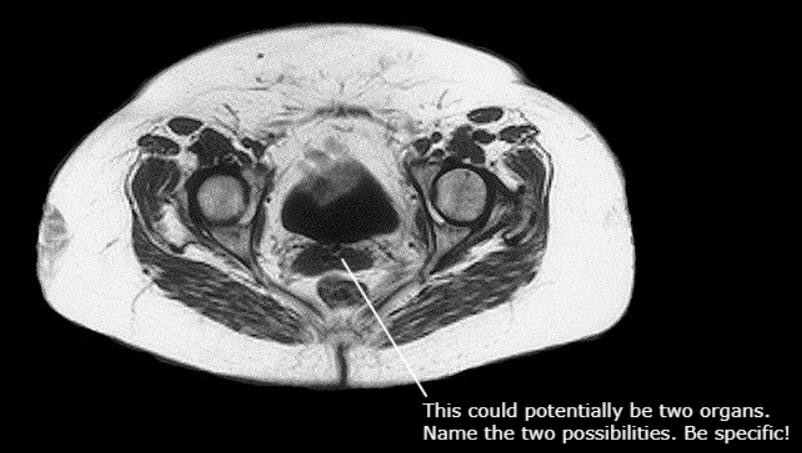

Cervix of the Uterus, Vagina